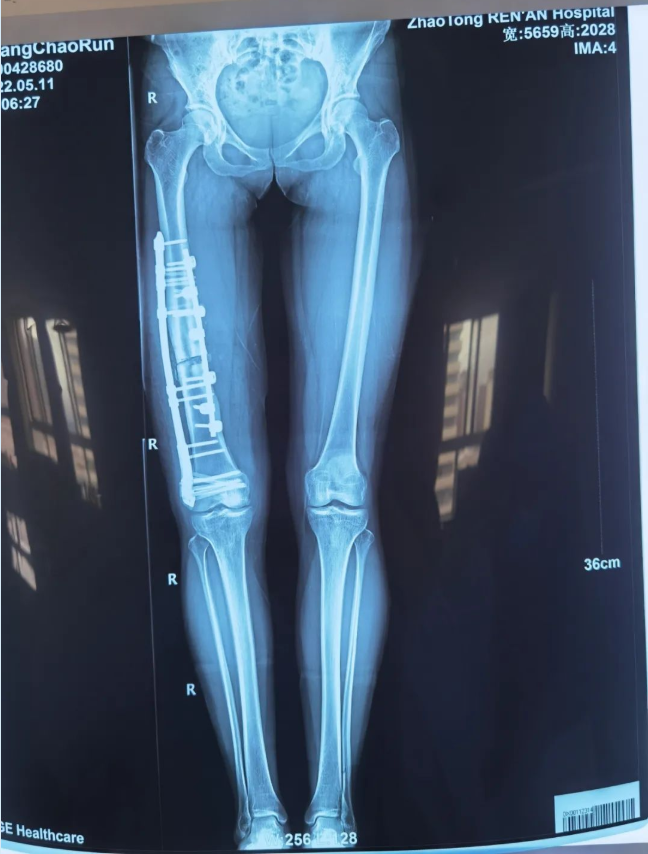

术后患者右下肢畸形完全矫正,双下肢等长,再经术后康复治疗,右膝关节活动自如,终实现多年正常步态、自信满满“潇洒走一回”的夙愿。

(术后影像)